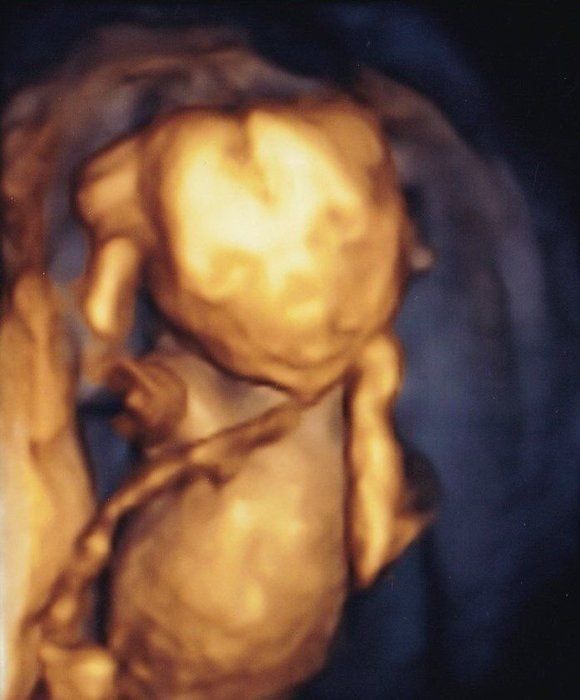

くろみつさんの妊娠18週目のエコー写真 男の子と判明し、「タロー」と命名

上半身の4D画像です。右手を頭に、左手を頬に置いている姿がなんともかわいらしく映っています。性別が男の子とわかったので「タロー」と命名。声に出すのは恥ずかしかったので、心の中で「タロー」と話しかけていました。つわりが終わったためか、食欲が湧いてきて、体重増加が気になりだしました。安定期に入り、お散歩を長めにしたり、プールで泳いだりもしていました。